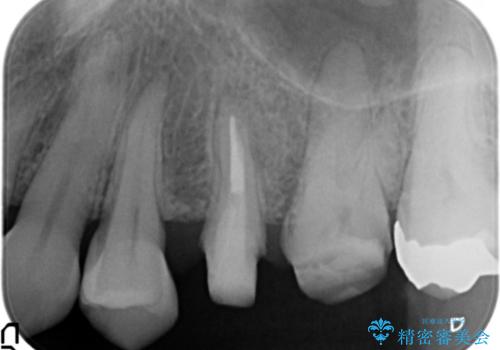

放置し崩壊した歯 セラミック治療による咬合機能回復

虫歯を丁寧に除去したのち、なんとか歯を残せる見通しがたったので根管治療を行いセラミック補綴を行いました。

今回は歯を残すことができましたが、早期の治療が歯の長い予後の期待値をあげます。